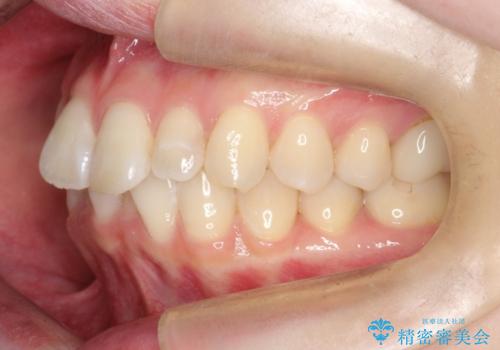

前歯のガタつきをマウスピース矯正で改善

- 前歯のガタツキが気になると来院されました。

奥歯の噛み合わせは綺麗に噛んでいたため、前歯の叢生(でこぼこ)に集中して治療するように計画しました。